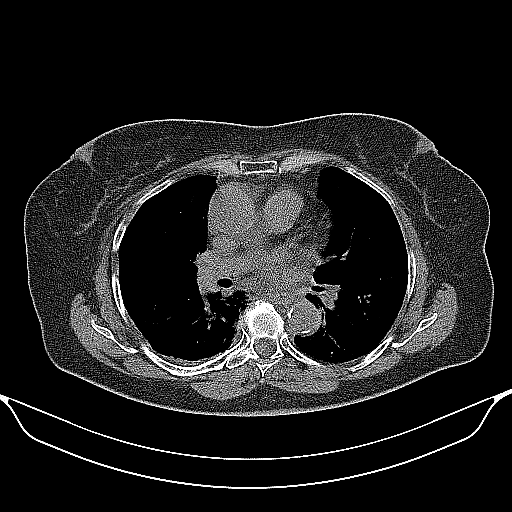

Image Grid

4Γ—3 grid: Rows show different image types (Original NATIVE, Reconstructed NATIVE, Original VENOUS, Generated VENOUS), Columns show windowing techniques (No Window, Lung Window, Mediastinum Window)

Original NATIVE CT scan (input)

Full window (WL 1023.5, WW 4095 β†’ Low βˆ’1024, High +3071)

Generated VENOUS CT scan (A→B translation)